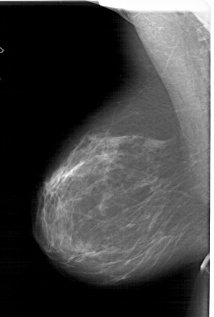

A_1813_1.LEFT_MLO

LEFT_MLO LINES 6016 PIXELS_PER_LINE 4051 BITS_PER_PIXEL 12 RESOLUTION 43.5 NON_OVERLAY